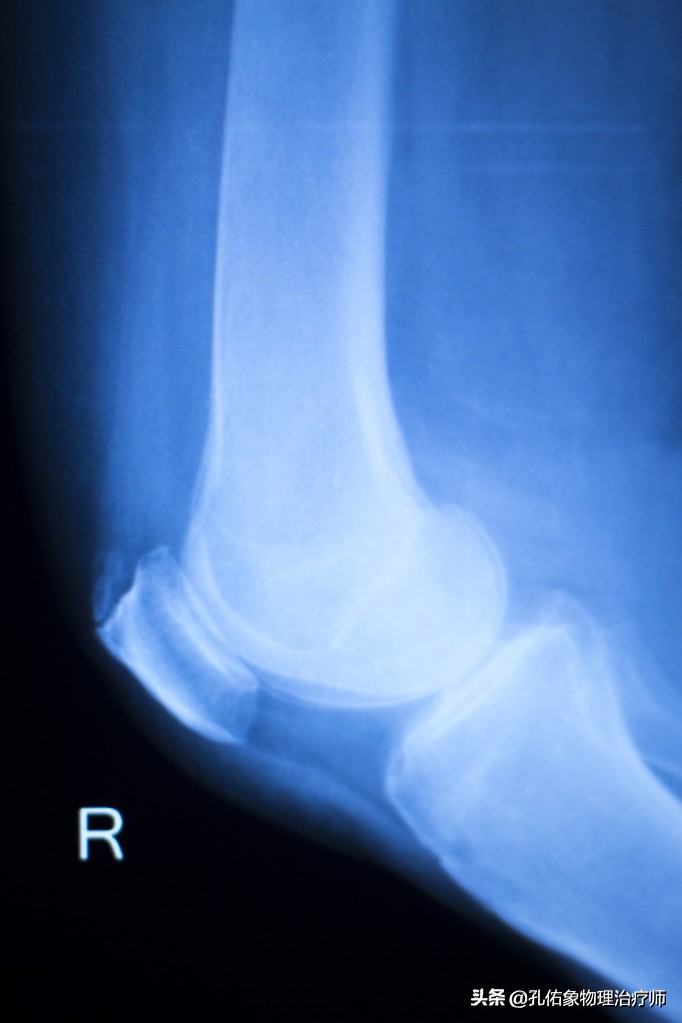

我们往往通过以上四个特殊检查就可以发现膝痛是不是膝盖骨的软骨软化所致?当然了,也可以去拍一张膝关节的正侧位片看看,一般早期疼痛往往在片子上也看不出啥问题,此时需要拍特殊体位的。

- 拍X片(轴位片)

一般在医院里边,很多医生也不会让患者去拍轴位片,都喜欢去拍正侧位片。但是对于膝痛早期的人而言,在下蹲过程中出现疼痛时的角度去拍轴位片,会发觉挺有意思的,膝盖骨是外移的,并没有在正常的髁间窝里边,这就是典型的膝盖骨软骨软化的表现。

这样的膝痛,在早期通过片子是很难发现的,所以你无论是做啥治疗,效果都不好。只有找到病因后,从根本的力学入手治疗才是上策。若是不及时治疗,使膝盖骨一直处于不正确的轨迹里面运动,最终膝痛厉害,活动受限,拍X正侧位片会显示膝盖骨边缘骨质增生、骨硬化改变及粗糙不平,膝盖骨关节间隙狭窄。